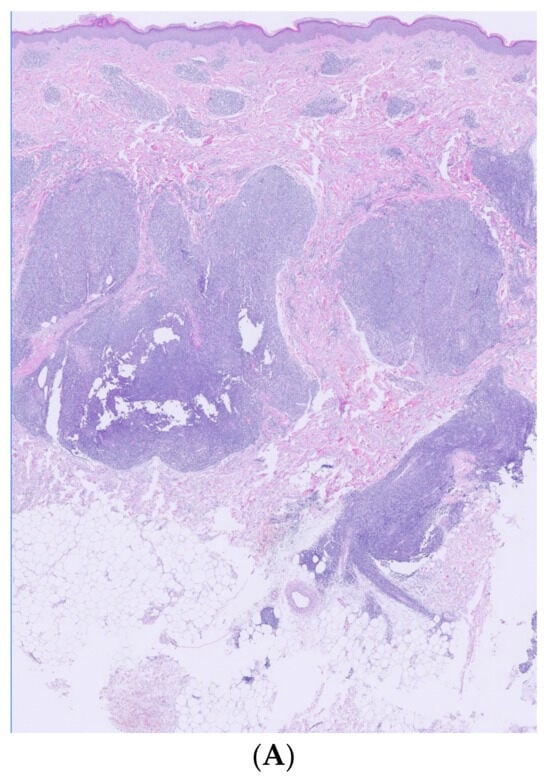

Histological and immunohistochemical examination of a lesion located on the right arm revealed a dense confluent lymphoid infiltrate that was predominantly perivascular and periadnexal, distributed in the superficial and deep dermis. The infiltrate consisted of small/medium CD3+/CD4+/CD5+/CD7+ cells with moderate cytologic atypia. Intermediate-sized elements were positive for PD1. Molecular analysis showed a positive rearrangement for TCR gamma, with T-cell clonality present in the analyzed lymphoid population. The proliferation did not exhibit epidermotropism, leaving a respected Grenz zone (Figure 2 and Figure 3).

Figure 2.

Histological examination. (A) (Hematoxylin/eosin ×2): large accumulations of lymphoid infiltrate, with perianexial and perivascular distribution located in superficial and deep dermis in minimal contact with hypodermis. (B) (Hematoxylin/eosin ×10): absence of epidermotropism, showing a respected Grenz zone. (C) (Hematoxylin/eosin ×40): dermal infiltrate composed of a heterogeneous mixture of mainly T and B lymphocytes.